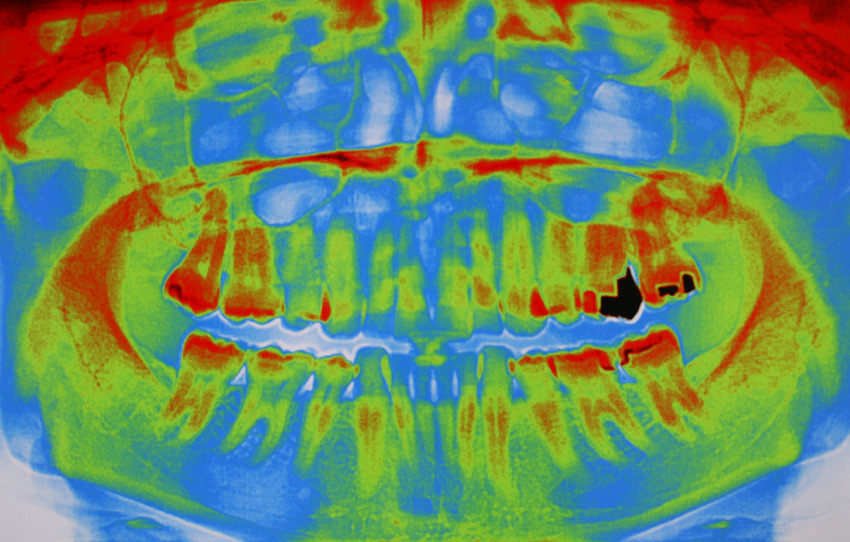

Unsere Praxis ist mit digitalen CCD Röntgensensoren der neuesten Generation ausgestattet. Diese ermöglichen gegenüber der konventionellen zahnärztlichen Röntgentechnik eine Reduktion der Strahlendosis um bis zu 90%. Darüber hinaus sind Auflösung und Kontrastverhalten der Bilder konkurrenzlos. Dies ermöglicht eine extrem schonende und exakte Diagnostik.